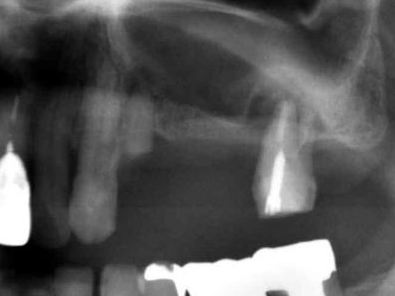

![]() |

| これは、インプラントを入れた当日に仮の歯をブリッジにしていれた状態のレントゲンです。 インプラントを埋入するときのトルクが35N(ニュートン)から40Nの範囲で埋めることができないと その場で仮歯を入れて咬めるようにして帰っていただくこと(即時荷重)が出来ません。 骨がある程度硬くないと無理ですし、また、軟らかい骨でも削るのではなく押し広げるように形成することによって このトルクを作るようにします。 最初のドリルの感じで、どのように押し広げれば 適正なトルクで埋入することが出来るかがイメージ出来なければ無理です。 また、骨の幅がギリギリでシミュレーションとの誤差が0.3mm以内の精度でしかも方向を合わせなければいけません。 文字通り職人技です。 これが出来る歯科医師は、兵庫県でも極少数だと自負しております。 |